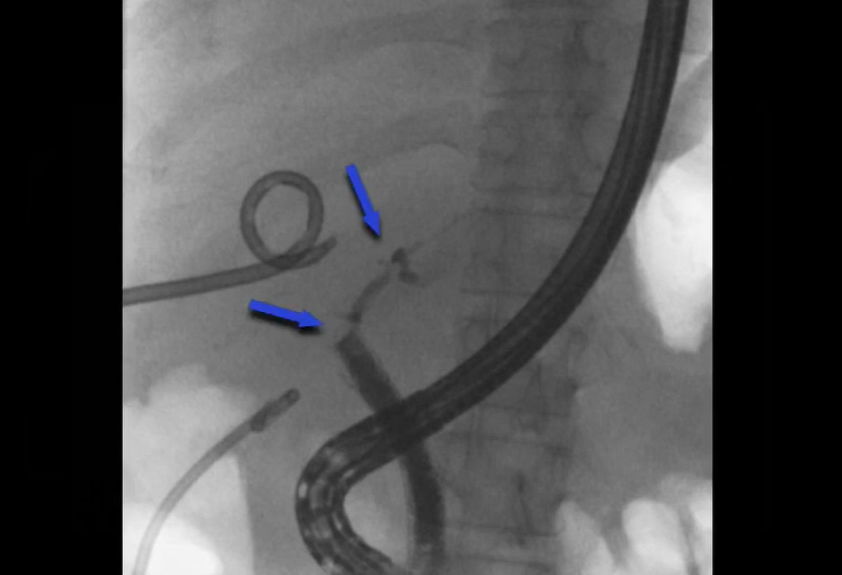

Retained common bile duct stent and stone impaction

Dr. Frizzell shares the case of an ERCP procedure using the EXALT Model D Single-Use Duodenoscope with SpyGlass™ DS Direct Visualization in an 86-year-old woman with a history of extended spectrum beta-lactamases Escherichia coli cholangitis due to a retained common bile duct (CBD) stent.